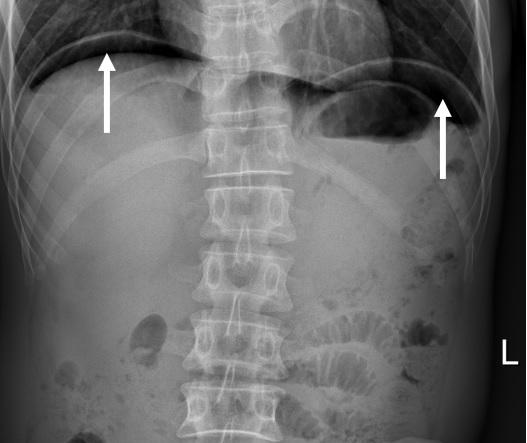

例如,怀疑胃肠道穿孔时,就应该站着摄片。这是因为胃肠道穿孔后,空气就会从这个破裂的“孔”中“跑”出胃肠道;站着摄片时,由于气体轻,会向腹部的最上方跑,从而积聚在胸腹部交界处的膈肌下;医生们就可以根据在膈下看到“新月状”气体影(见下图)做出诊断,而如果是躺着照的卧位腹部平片就发现不了。

膈下新月状气体影(白箭)提示胃肠道穿孔。如果是躺着照,是显不出来的